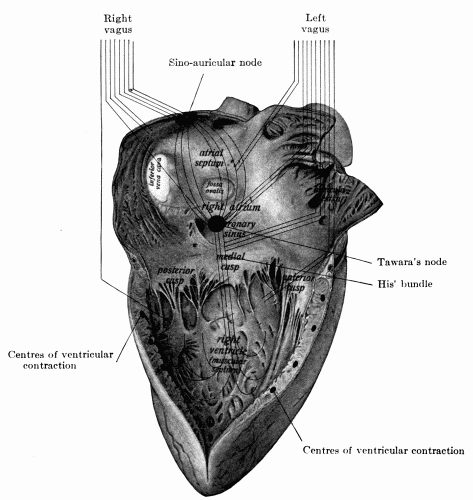

38. Right side of the heart showing distribution of the two vagus nerves127

53. Schematic distribution of right and left vagus145